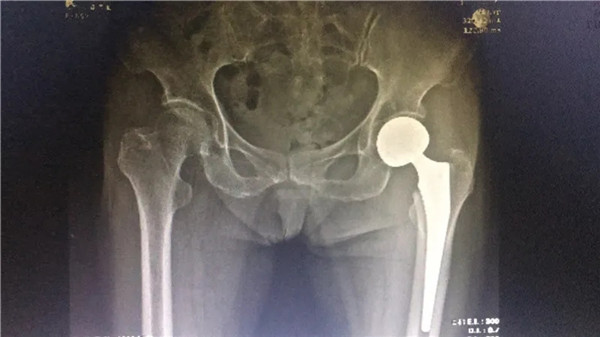

術(shù)后

6月4日,在完善各項術(shù)前檢查,身體狀況符合手術(shù)指征后,陳阿婆接受了左髖關(guān)節(jié)置換術(shù)。手術(shù)由危立軍副院長主刀,一個半小時后,手術(shù)圓滿成功。術(shù)后,陳阿婆恢復(fù)良好,一周后,便可以下地行走。術(shù)后半個月,陳阿婆出院回家休養(yǎng)。